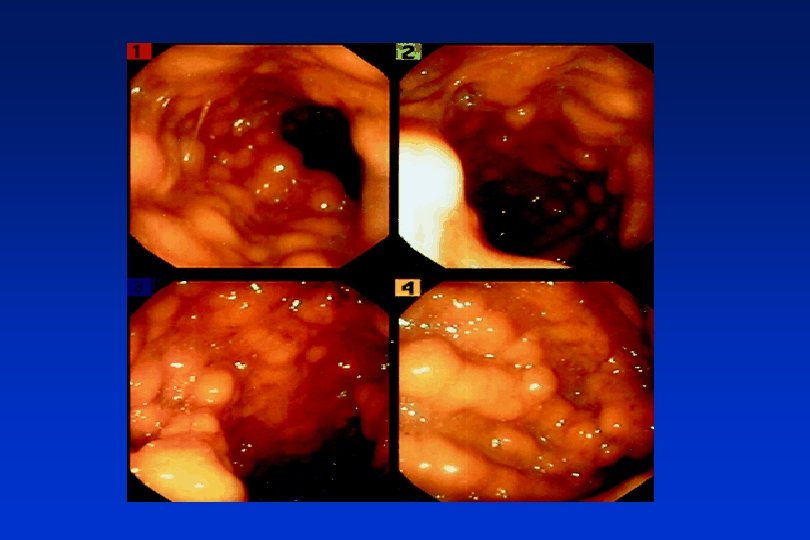

Amebic colitis

CDI – clinical forms a) asymptomatic carriers (2 -3 % of adults, in children much more, prevalence is increasing with the length of hospitalization - 10 -25 % or more) b) uncomplicated colitis (diarrhea, fever, no pseudomembranes) c) pseudomembranous colitis - PMC (sepsis, leucocytosis, abdominal pain, and bloody stool) d) toxic megacolon (paresis and necrosis of the gut, possible perforation, infectious shock)

Diagnosis of CDI • antibiotics in history • clinical findings • microbiological testing – detection of toxins (ELISA), specific antigen (GDH), culture, cytotoxic test, PCR • coloscopy (pseudomembranes) • ultrasound, CT – auxilliary methods